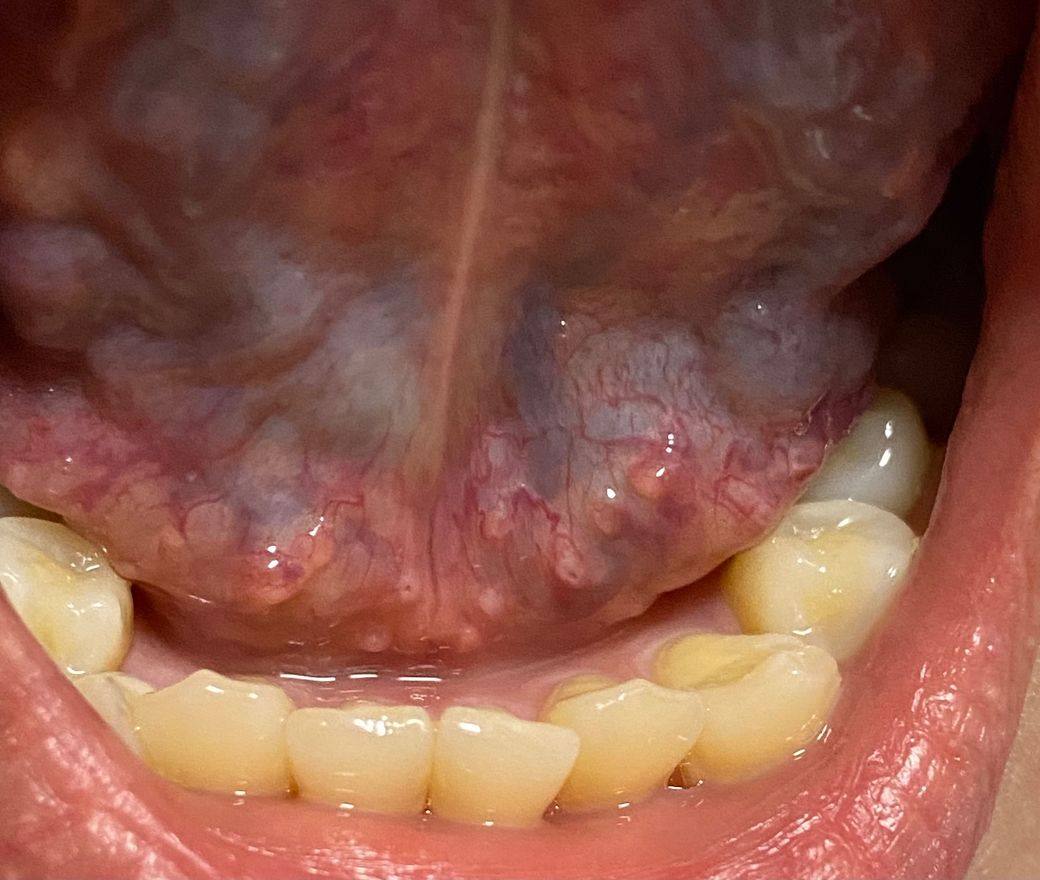

혀 밑에 수포?돌기? 같은게 작게 났는데 뭔지 모르겠어요

혀 옆에 구내염이 생겨서 혀 구석구석 봤는데

혀 아래에 작게 따닥따닥 뭐가 난 걸 발견했습니다

건드렸을 때 가렵지도 아프지도 않은데 뭔지 알 수 있을까요??? 병원에 가서 진료받아야 할까요???

그리고 혀 아래에 빨갛게 동그라미친 부분은 누르면 아픈데 크기가 저렇게 작아도 구내염이라고 볼 수 있나요??

• 1번 째 사진

올려주신 상기 병변은 질환에 의한 병변이 아니며 혀점막의 정상적이 구조물과 판단이 됩니다. 혀나 구강 점막은 다양한 형태로 나타날 수 있는데 표면의 결절성 변화나 궤양이 형태로 나타난다면 염증 병변과 종양성 병변에 대한 감별이 필요합니다. 하지만 올려주신 사진상 이러한 특징적인 소견은 관찰되지 않으므로 정상적인 점막의 변화로 판다할 수 있습니다. 따라서 증상이 없다면 진료 없이 경과 관찰이 가능하므로 너무 걱정하지 않으셔도 되겠습니다.